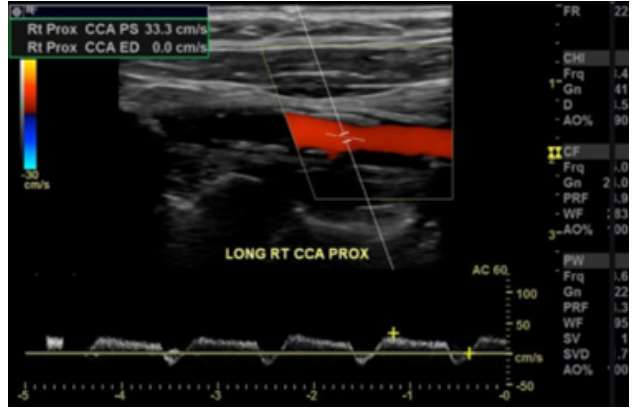

Observe a imagem a abaixo, extraída de um estudo da carótida comum direita.

Assinale a alternativa CORRETA.